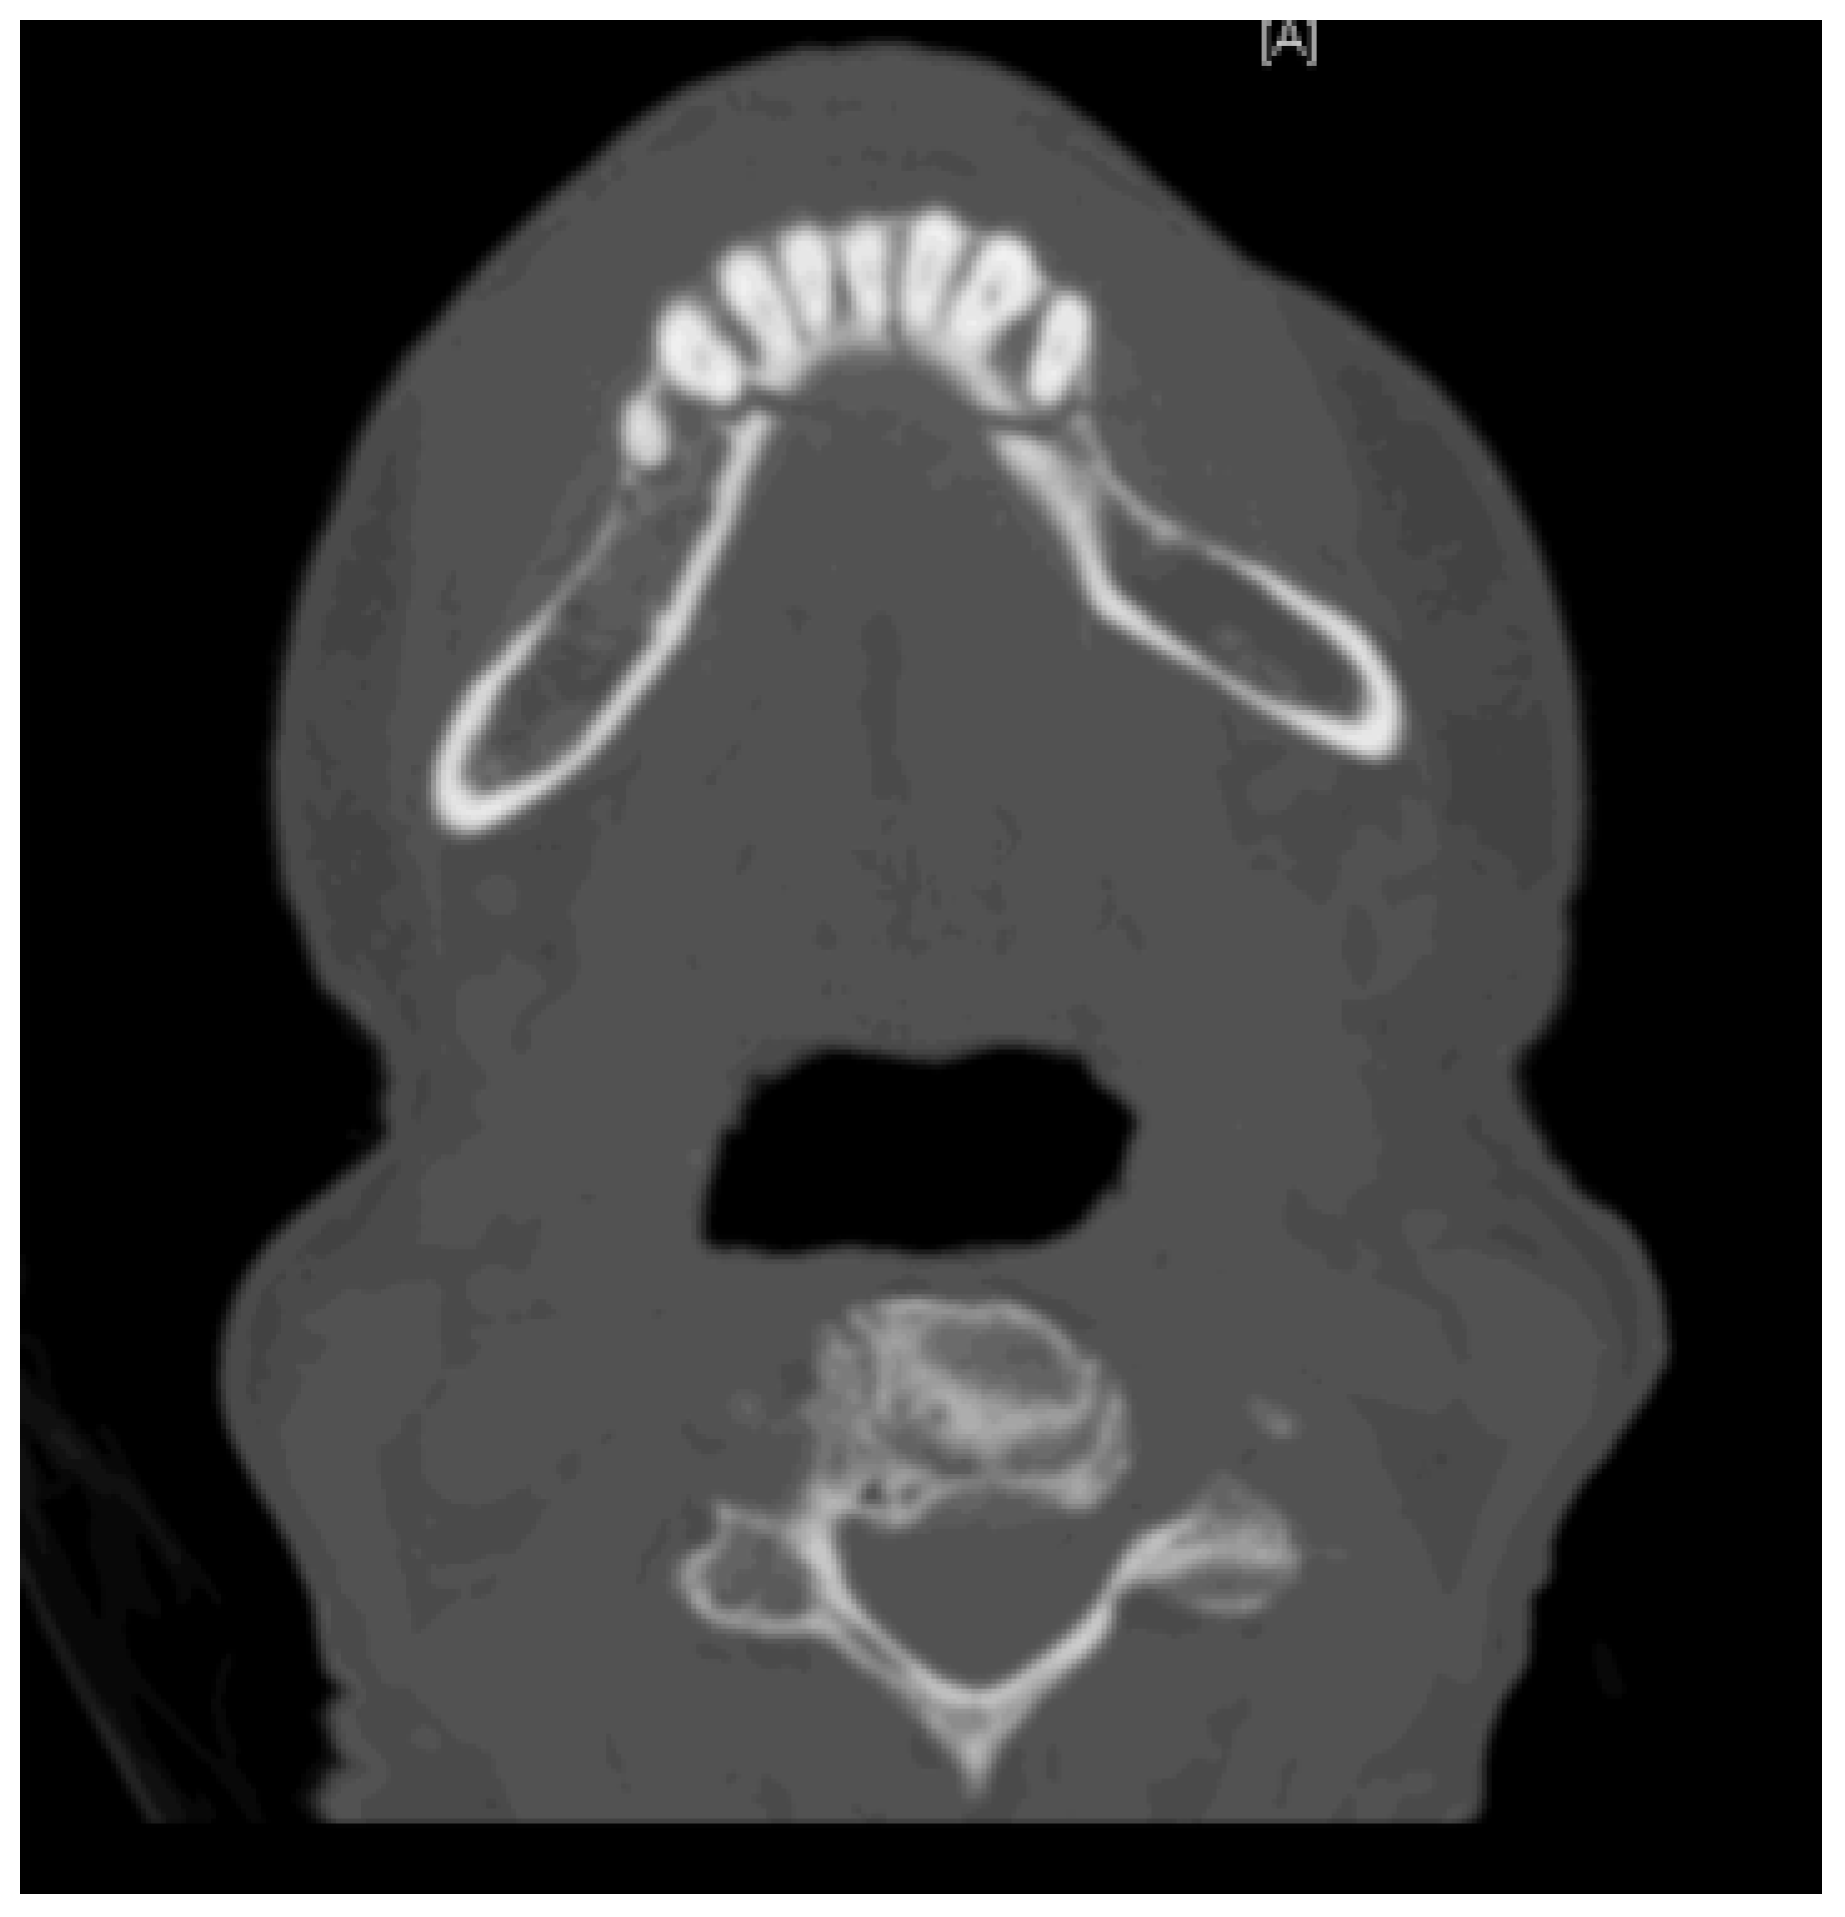

2.1. Case 1

2.2. Case 2